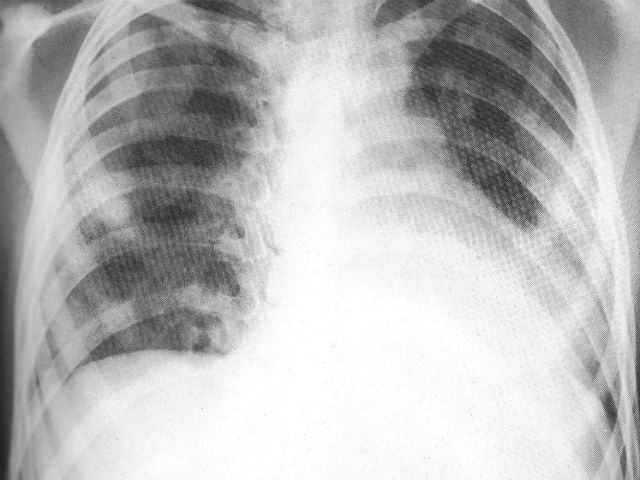

ROMA – Ogni 25 secondi nel mondo un bambino muore di polmonite, per un totale 3.400 decessi al giorno.

Lo ricorda l’Unicef, il fondo delle Nazioni Unite per l’infanzia, in una nota diffusa in occasione della quarta giornata mondiale contro la polmonite. ‘La polmonite da sola e’ la principale malattia killer dei bambini sotto i cinque anni a livello mondiale- spiega l’Unicef – e’ necessario percio’ un maggiore sforzo per debellare questa malattia, che e’ facilmente prevenibile con cure poco costose’.